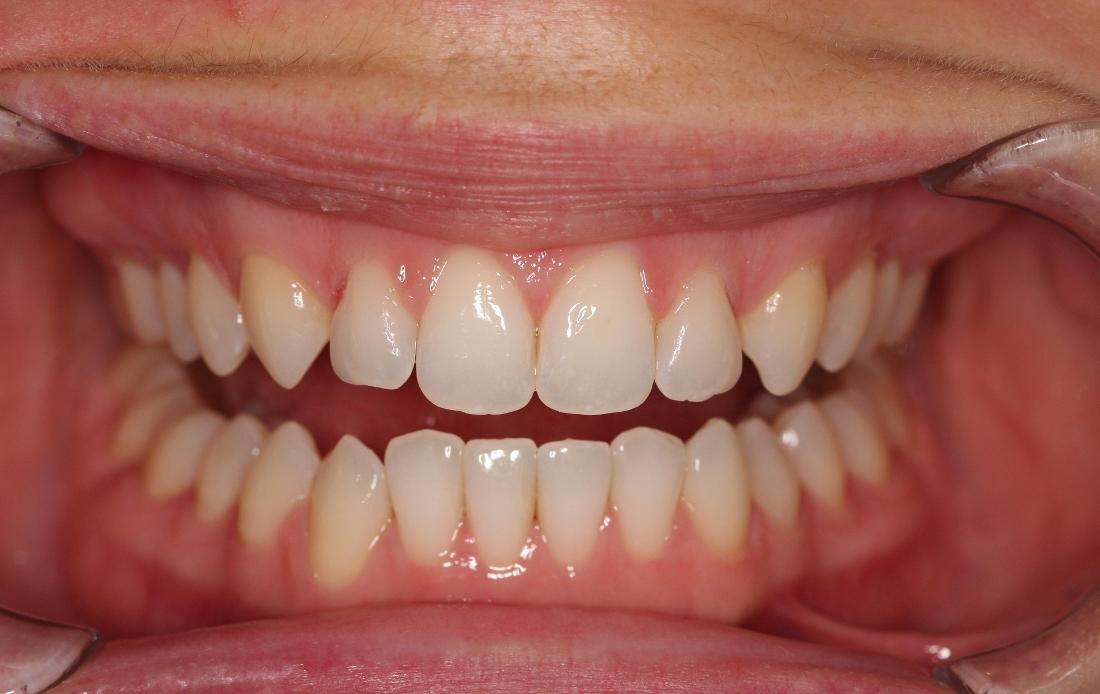

This young woman was self conscious about the crowding in her upper and lower teeth. After months of invisalign treatment, she is very satisfied with the result.